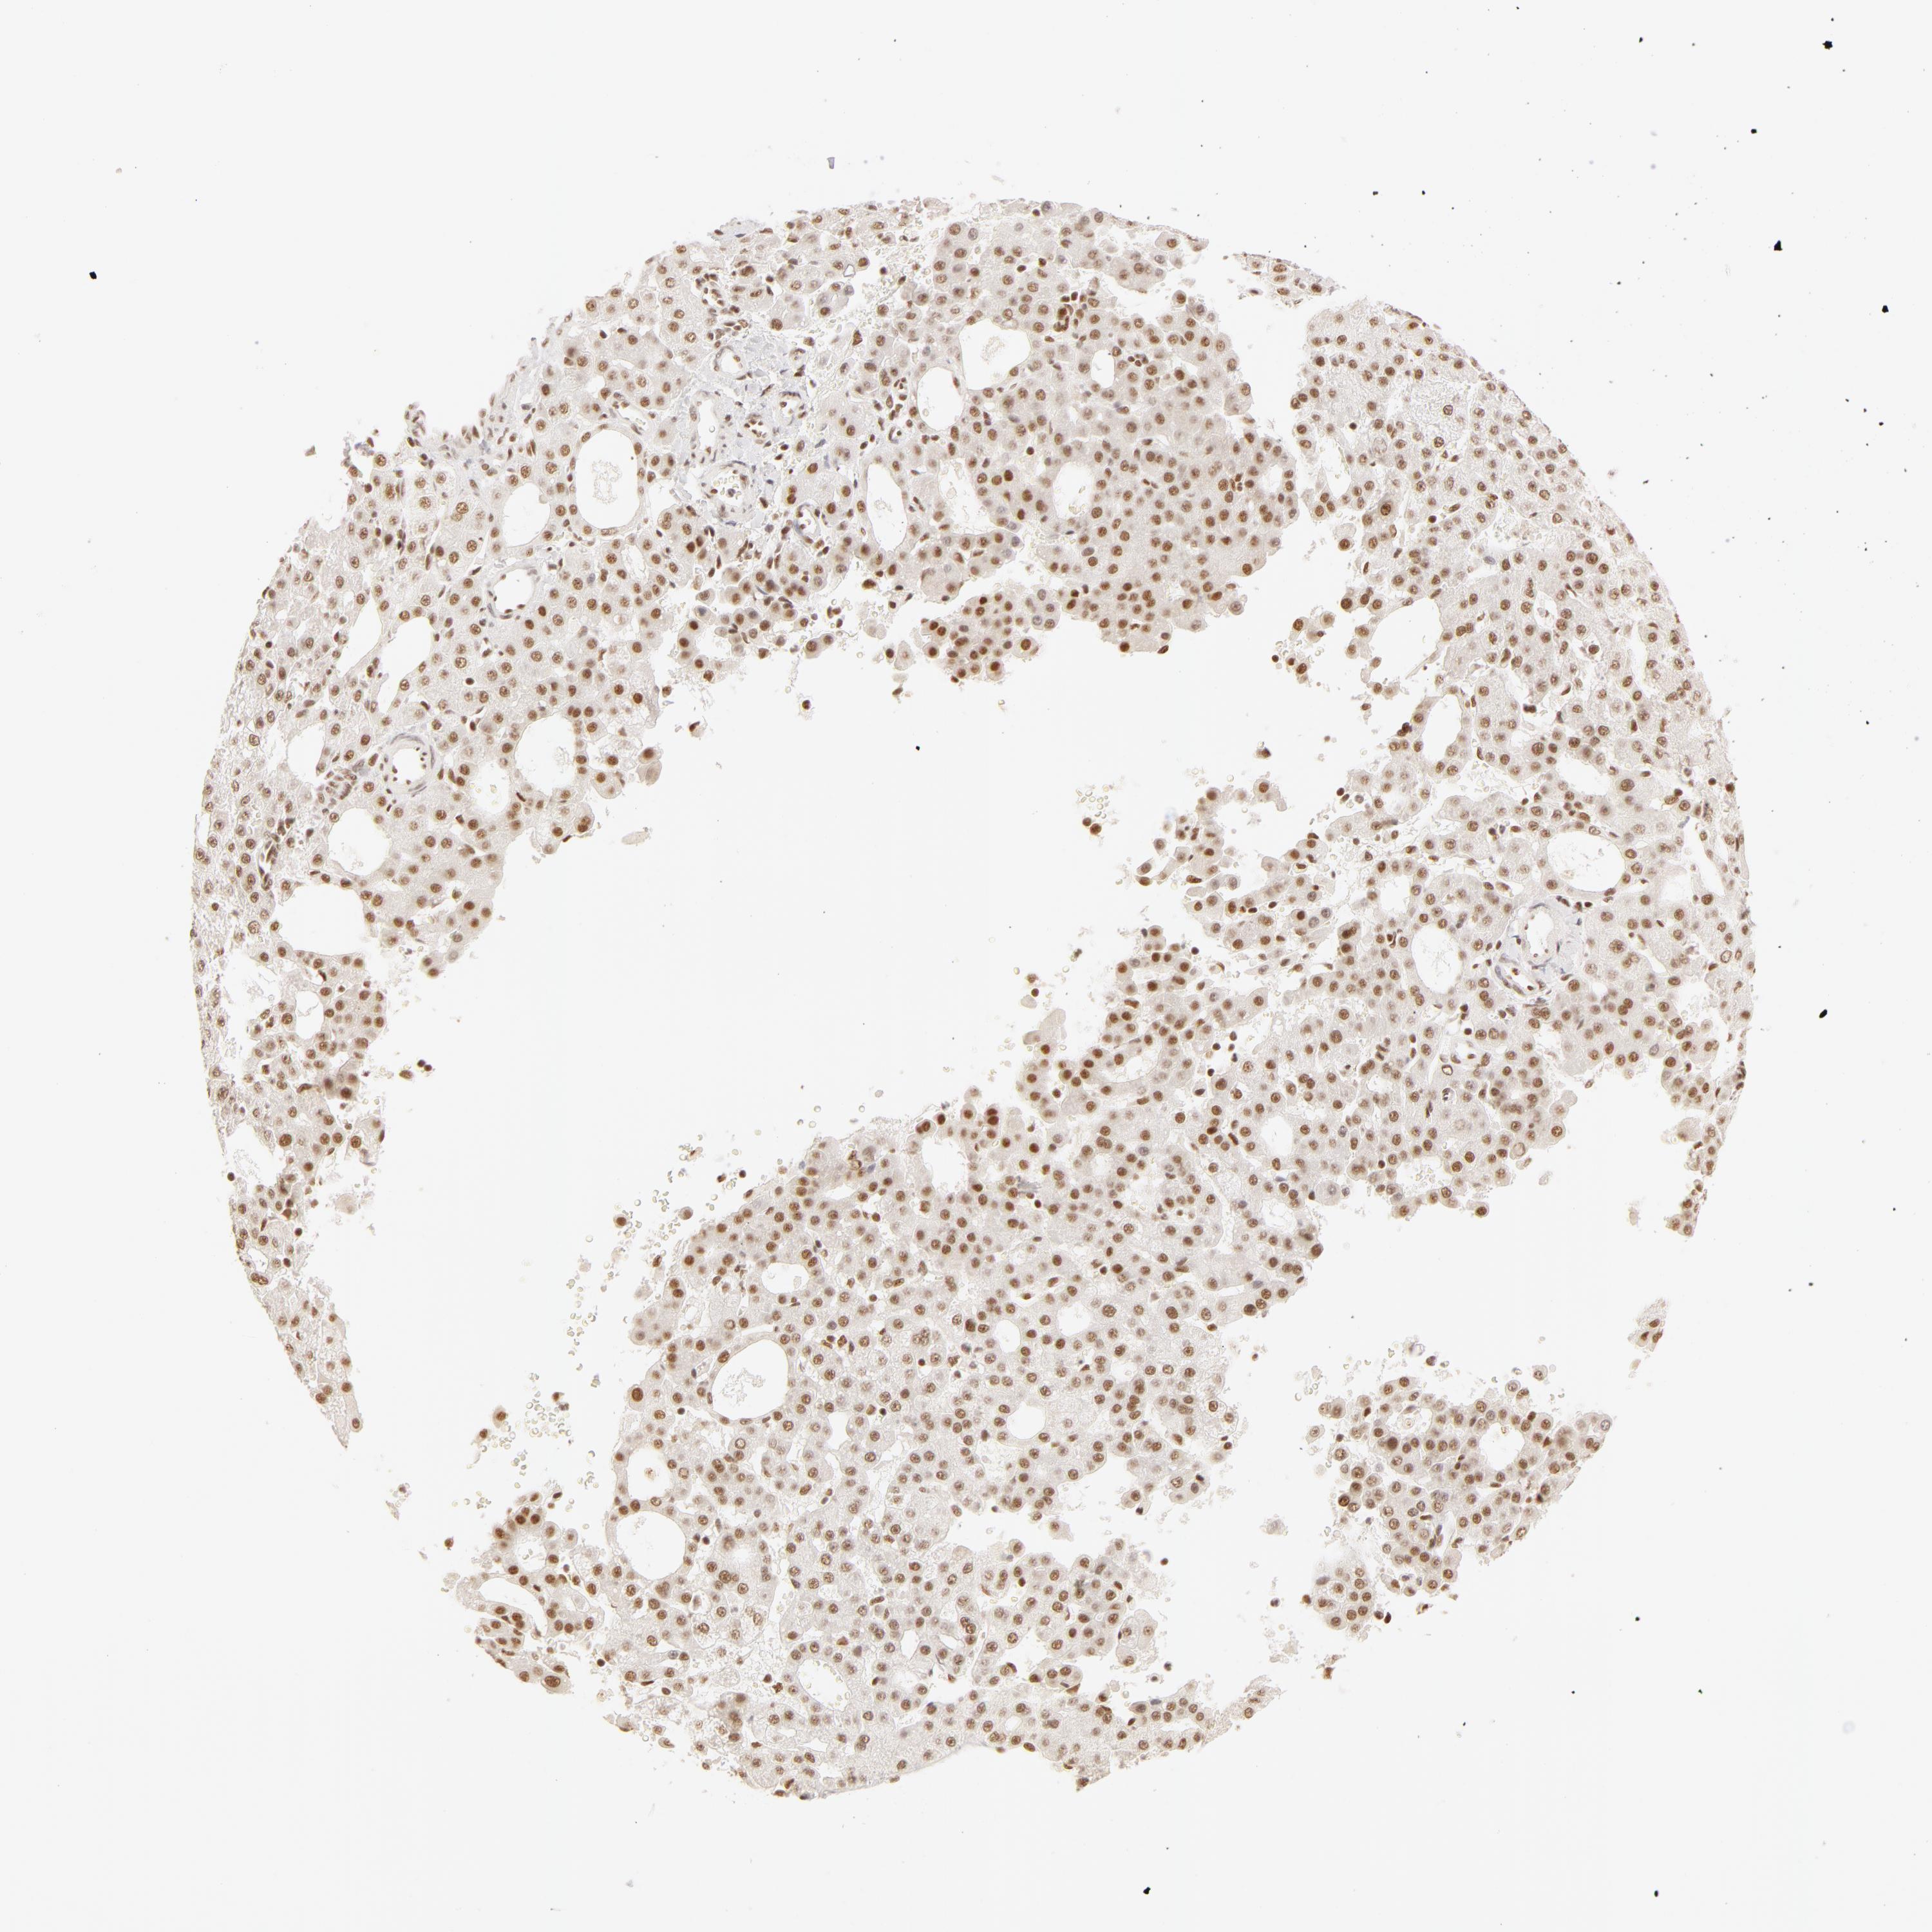

LIVER CANCER - Protein expressioni

A mouse-over function shows sample information and annotation data. Click on an image to view it in a full screen mode. Samples can be filtered based on level of antibody staining by selecting one or several of the following categories: high, medium, low and not detected. The assay and annotation is described here.

Note that samples used for immunohistochemistry by the Human Protein Atlas do not correspond to samples in the TCGA dataset.

Antibody stainingi

Antibody staining in the annotated cell types in the current human tissue is reported as not detected, low, medium, or high, based on conventional immunohistochemistry profiling in selected tissues. This score is based on the combination of the staining intensity and fraction of stained cells.

Each image is clickable and will lead to virtual microscopy that enables deeper exploration of all samples and also displays staining intensity scores, fraction scores and subcellular localization as well as patient and tissue information for each sample.

Antibody HPA001591

Staining

High

Medium

Low

Not detected

Intensity

Strong

Moderate

Weak

Negative

Quantity

>75%

75%-25%

<25%

None

Location

Nuclear

Cytoplasmic/membranous

Cytoplasmic/membranous,nuclear

Carcinoma, Hepatocellular, NOS

Cholangiocarcinoma